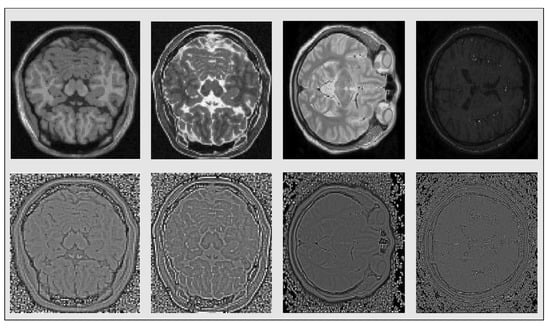

In MR Images the contrast depends on the magnetic properties and the number of hydrogen nuclei existing in the area being imaged. Common type MR Images include and -weighted resulting from different timing radiofrequency pulse sequences, Proton Density (PD) that display the number of nuclei in the area and magnetic resonance angiography (MRA) that highlights movement in the body’s blood vessels, among others. These different types are presented in Figure 3. Examining different types of medical images, such as different types MRIs, CT images etc, that have totally different intensity distributions, can often be presented as a problem of strong photometric distortions, so we are going to address it as such in the next subsection.

Figure 3.

Original , , Proton Density (PD) and magnetic resonance angiography (MRA) images respectively (first row) and their SQI’s counterparts after thresholding (second row).

with a data-dependent parameter that can be used to have additional control over the value of threshold and use it for “denoising” purposes. In all the experiments we conducted we set that parameter equal to . The SQIs resulting from the application of the above-mentioned procedure on the photometrically distorted images and the four different contrast type MRI slices, are shown in Figure 2 and Figure 3 respectively. Having filtered out the strong photometric distortions, we can use the above mentioned area-based technique to solve the groupwise alignment problem.